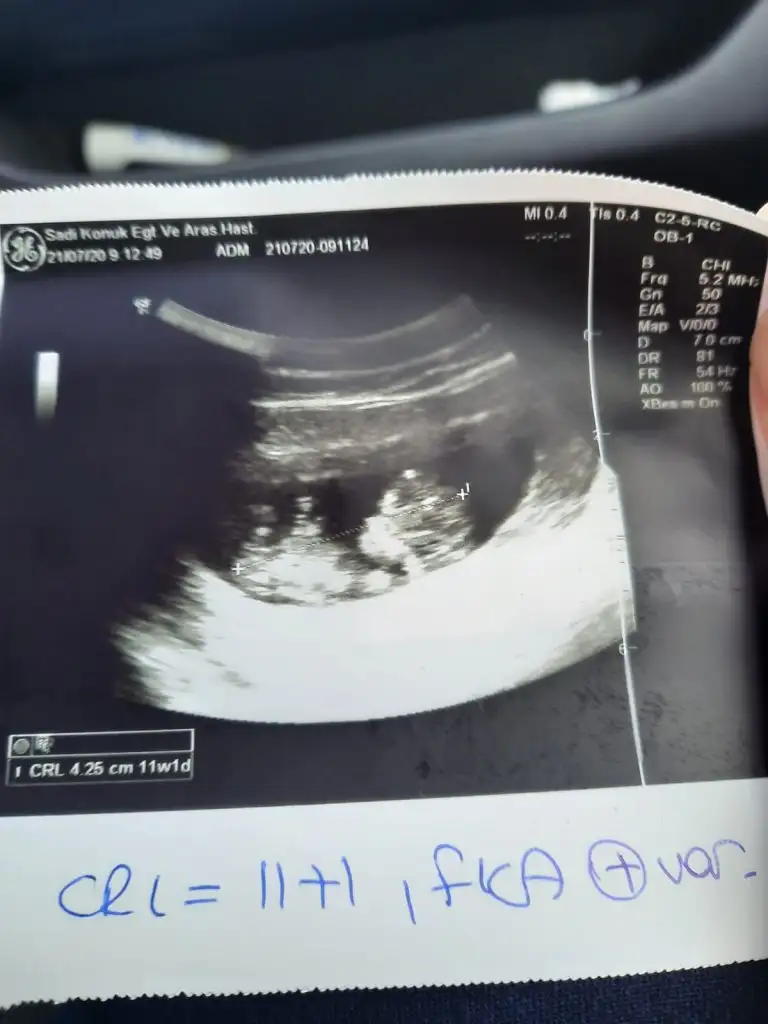

Kiz olabilirmikızlarrr merhababugun doktor kontrolüm vardı 2 li test için gittim cumaya randvu verdiler.

bebiş çok büyümüş. 14 gün geriden geliyordu 9 güne inmiş. normalde 12+3 haftalığım. 2 kilo aldım

bulantı kusmam yok. karnım da çıkmaya başladı. allahımm herkesin bebişleri çok iyi olsunnn... aminnn

cinsiyet tahminleri alayım :)

öyle diyen çok oldu tabi bilmiyorum hiç bir fikrim yok ilk bebişim sadece fotosuna bakıp gülümsüyorum :) :)Kiz olabilirmi